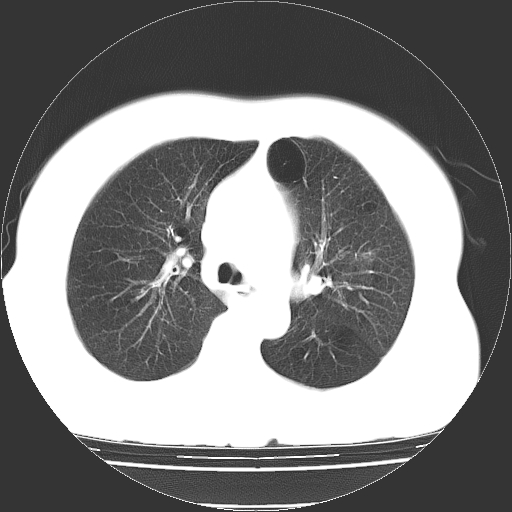

标题: CT13141:女,70岁,咳嗽、胸闷半个月。 [打印本页]

标题: CT13141:女,70岁,咳嗽、胸闷半个月。

女,70岁,咳嗽、胸闷半个月。纵隔窗未见异常,未上传。

慢支炎、肺气肿征,双肺多发肺大泡

小叶中心型肺气肿并多个肺大泡形成。

小叶中心性肺气肿及间隔旁肺气肿.(多与吸烟有关)